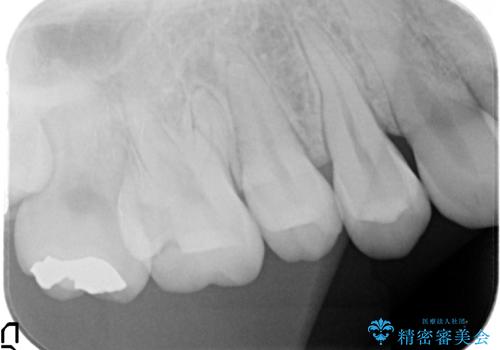

- 右上奥歯の古い樹脂と銀歯をセラミックにやり替えた症例です。

右上67の樹脂及び銀歯を除去後、セラミックインレーにて修復を行いました。